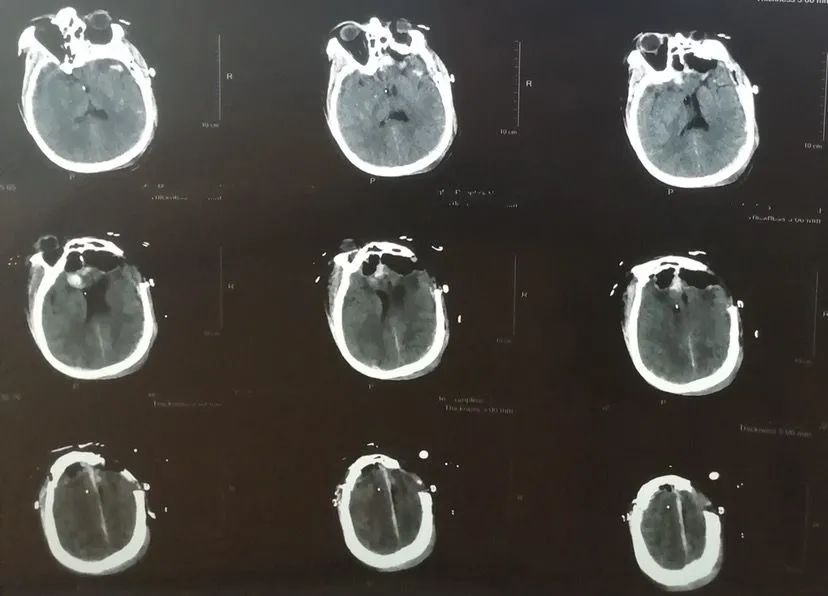

患者男性,48岁。2020年10月头部外伤,头颅CT显示双额叶脑挫裂伤,于当地医院行左额颞开颅血肿清除+去骨瓣减压术。